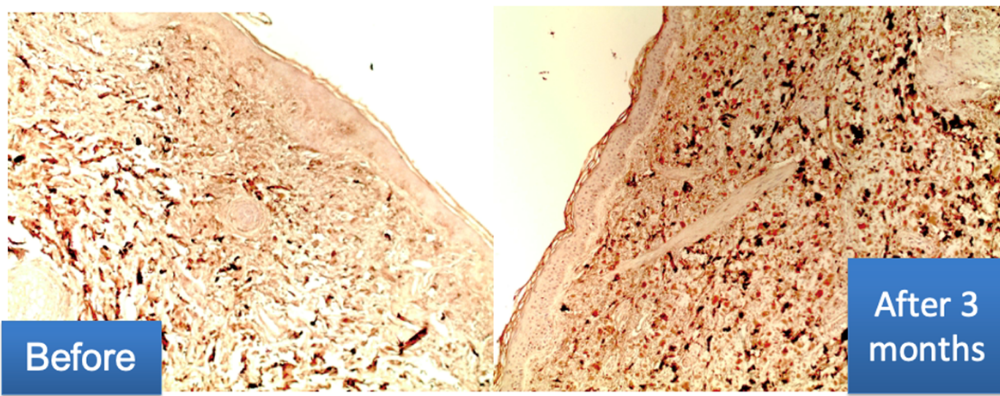

Immunohistochemical examination:

- The content of collagen III in the dermis is notably increased

- The formation of longitudinally oriented fibers